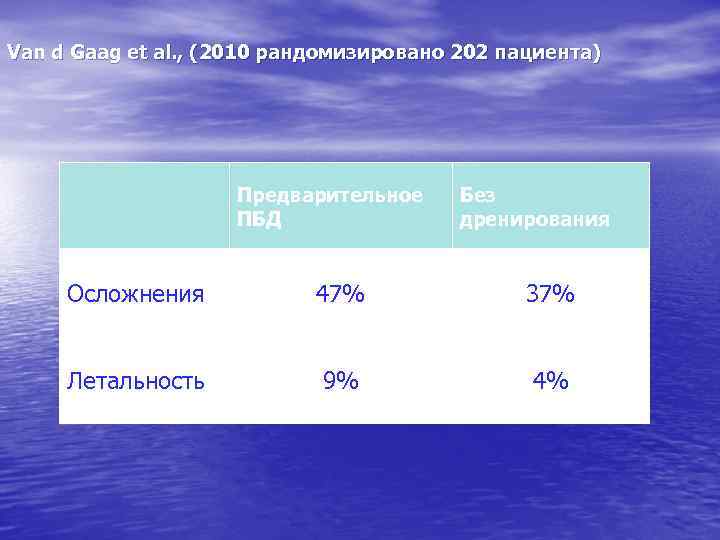

Van d Gaag et al. , (2010 рандомизировано 202 пациента) Предварительное ПБД Без дренирования Осложнения 47% 37% Летальность 9% 4%